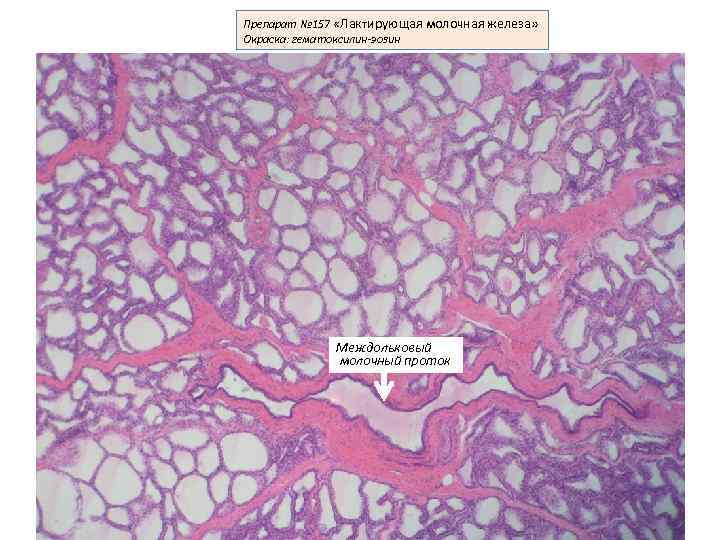

Исследование: микропрепарат молочной железы в медицине

Раздел: Снимки-откровения